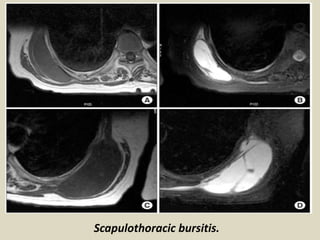

Scapulothoracic bursitis and snapping scapula:

Snapping scapula syndrome usually is a result of abnormal anatomy, abnormal

scapulothoracic motion, space-occupying bony or soft-tissue lesions or a combination of

these. Imaging is commonly used to determine the nature and location of snapping scapula

syndrome and is essential in treatment planning. Conventional radiographs normally are

the first diagnostic step, but since the anterior aspect of the scapula is difficult to visualize

and soft tissue masses are not well visualized on plain films, additional cross-sectional

imaging is commonly performed.

Ultrasound & Magnetic Resonance Imaging

MRI is usually performed when soft tissue pathology is expected and is especially useful

in the diagnosis of bursitis and soft-tissue masses. Ultrasound is less useful than

MRI since the majority of the scapulothoracic joint can't be visualized, but it is

commonly used to guide needle placement in bursitis for diagnostic and therapeutic

injections. On ultrasound bursitis is seen as a fluid filled bursa which usually is anechoic

and does not show any internal vascularity. On MRI bursitis is seen as a well-

demarcated cystic mass with low signal on T1-, high signal on T2 weighted

sequences and rim enhancement after administration of intravenous

contrast. Adventitial bursae may show a more ill-defined area of low T1- and high T2

signal intensity. Soft tissue tumors are another cause of snapping scapula syndrome

with elastofibroma dorsi being the most frequently seen tumor responsible for it.

Scapulothoracic bursitis.

(A) Coronal and (B) axial T1-weighted images) demonstrate a well-demarcated low signal intensity lenticular mass.

(C) Coronal and (D) axial T2-weighted images shows high signal intensity mass situated at the subscapular region

between the serratus anterior and the rib cage. SC: subscapularis muscle, LD: latissimus dorsi muscle, SA: serratus

anterior muscle. Gadolinium enhanced (E) Coronal and (F) axial T1-weighted image shows rim-like enhancement.